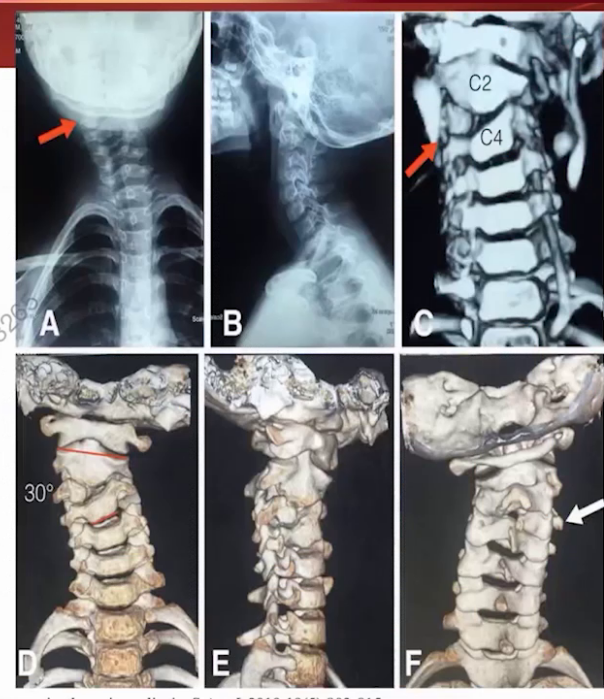

脊柱全长X线显示C4-T1侧弯角度57.7度,双肩高度差2.8cm,冠状位和矢状位基本平衡;局部参数显示半椎体畸形角度达44.7度,颈椎后凸角度25度,颈部活动度正常。

CT显示C5-C7椎体分界不清,伴对侧骨桥形成。三维重建更清晰展示局部畸形结构。